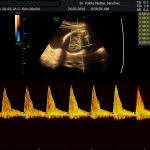

Modalidad de imagen ecográfica que permite evaluar flujos arteriales y venosos en estructuras fetales, placentarias y maternas obteniendo información valiosa sobre

- La oxigenación feto placentaria (bien estar fetal)

Este modo ecográfico nos brinda datos importantes desde la 6ta a la 40ta semana de embarazo. Nosotros la utilizamos en todos nuestros exámenes ecográficos.